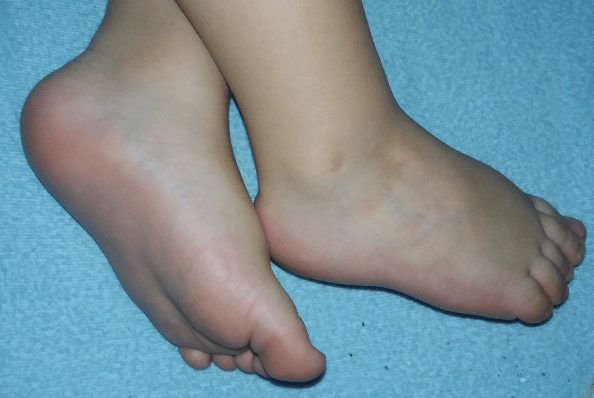

Dziewczyny powiem Wam, że gdybym nie słyszała o chorobie SKS w życiu bym nie powiedziała, ze coś jest nie tak że stopkami. A że synuś to ma to ja po prostu każde złe staniecie na nozce i już panikuje. A naprawdę widzę nieraz różne dzieci i mają zdrowe nogi a chodzą tak do środka, że masakra. Więc sama widzicie. Ja teraz po synka SKS jestem taka przewrazliwiona i w każdych stopach praktycznie coś widzę. Wy też tak macie?

Synek jak spi to tak trzyma nóżki :-)

I chce Wam jeszcze pokazać zgiecie stopki. Przepraszam, że tak trzymam wiem, że powinno się przyłożyć cala dłoń do stopy, ale niestety tylko tak dałam radę przytrzymać nozke, bo druga reka musialam robic zdjęcie :-)

Mysia1o02 oj tak. Wszędzie doszukuje się że coś nie tak jest. Stópki jak śpi wyglądają ładnie. Kurczę chcialam dodać zdjęcia ze zgieciem i mi wyrzuca że plik za duży.

Milenka887 to mąż panikuje ☺. Stawia moim zdaniem ładnie stópki.

Dzięki za pomysł ze screenem ☺. U nas tak wygląda zgiecie grzbietowe.